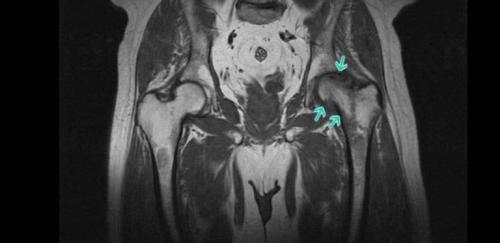

Как восстановить хрящевую ткань тазобедренного сустава. Диагностика

При возникновении признаков коксартроза рекомендуется как можно раньше обратиться к ортопеду. Изначально врач проведет опрос больного и выяснит характер предъявляемых жалоб, а затем перейдет к осмотру и выполнению функциональных тестов, сравнению длины ног. Как правило, полученных данных достаточно для того, чтобы с большой долей уверенности говорить о наличии коксартроза.

Но поскольку подобная клиническая картина может сопровождать и ряд других заболеваний тазобедренных суставов как воспалительной, так и невоспалительной природы, обязательно назначаются инструментальные методы диагностики. С их помощью специалист сможет не только подтвердить наличие коксартроза, дифференцировать его от корешкового синдрома, обусловленного патологиями позвоночника, но и правильно оценить степень его развития, а значит подобрать наиболее эффективную тактику лечения.

Сегодня для диагностики коксартроза используются:

- Рентген тазобедренных суставов – получаемые снимки позволяют обнаружить признаки деструктивных изменений, наличие остеофитов, характер деформации костных структур и измерить толщину суставной щели.

- КТ – более современный метод диагностики патологий костей, предоставляющий более четкие данные, чем рентген, но отличающейся большей стоимостью. Поэтому КТ назначают в спорных случаях, когда требуется уточнить диагноз и степень разрушения тазобедренного сустава.

- МРТ – высокоинформативный метод исследования суставов, предоставляющий максимальное количество информации о состоянии сустава и всех его структур, в особенности гиалинового хряща, связок и особенностях кровоснабжения.

При диагностировании коксартроза обязательно проводится комплексное обследование организма с целью установления причин, повлекших за собой развитие дегенеративно-дистрофических изменений в тазобедренном суставе. Поэтому пациентам назначается ряд лабораторных анализов, в том числе ОАК, ОАМ, ревмапробы, биохимический анализ крови и другие.